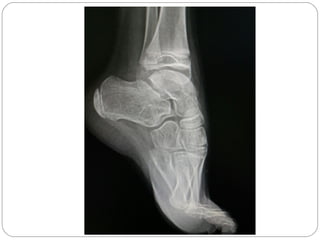

PIE PLANO RIGIDO

Raro

Menos del 0.1 %de los casos

DOLOROSO

B) ADQUIRIDO:

-lesiones inflamatorias que comprometan la articulación

subtalar y medio tarsianas (artritis juvenil, postraumática, etc).

-COALICION TARSAL: adolecentes.

Limitación dolorosa de la articulación subastragalina.

Antecedentes de esguinces de tobillo de repetición

Rx disminución del espacio subastragalino.